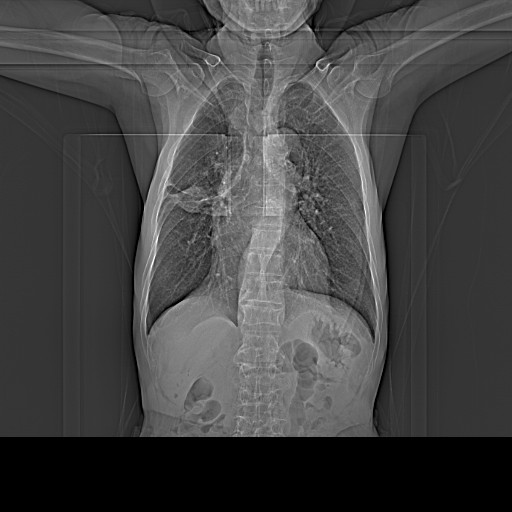

CT49778:胸部病变

本帖最后由 cefcmj 于 2015-1-19 11:44 编辑 男,76y 憋喘10天

慢支、肺气肿,右肺结核瘤。

右肺中叶阻塞性病变,结核可能性大,建议纤支镜检查。

纵隔内及肺门处多发钙化淋巴结,肿块内亦见散在钙化灶,结核球可能性大

右肺结核瘤。

矽肺并结核

右肺上叶后段的病变,内有散在的多发钙化灶,周围有纤维条索样病灶,后段支气管充气证,肺门多发钙化淋巴结,考虑结核瘤可能性大。

双肺支气管炎,肺气肿。